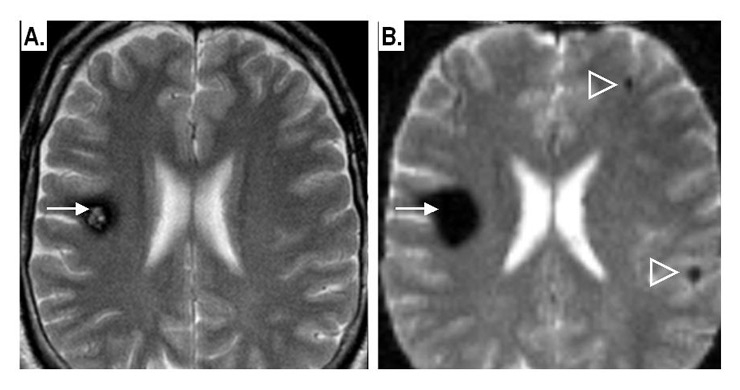

Figure 4

Example of supra-tentorial intra-parenchymal CMs:

A: conventional T2-weighted spin-echo MRI image: shows a solitary CM (arrow) in the right frontal lobe. The lesion shows a “pop-corn” appearance surrounded by a dark rim of haemosiderin.

B: Same patient, same axial section, T2-weighted gradient-echo, echoplanar image: notice the “blooming effect” due to susceptibility artefacts by the CM-related haemosiderin, with two small lesions now detectable in the contralateral hemisphere (arrowheads).

CT has a sensitivity of 36–74% [21, 24] to detect CMs by exhibiting a space-occupying effect, focal nodular hyperdensity and calcifications on unenhanced CT and mild enhancement on CT after intravenous iodinated agents [25]. MRI remains the method of choice for the detection of CMs. The signal behaviour is determined by the stage of bleeding or thrombus and thus the haemoglobin form in the lesion. Characteristic appearances include the “popcorn” as well as the rare “fluid-fluid level” pattern (fig. 5C). The susceptibility-weighted MRI uses the “blooming effect” due to the susceptibility effects of the blood by-products to enhance lesion detectability (fig. 4B). CMs present with variable degrees of contrast enhancement and, thus, are definitely not distinguishable from AVM when assessed with contrast-enhanced MRI (fig. 5A) [26]. A classification of CMs based on MRI was originally proposed by Zabramski [27, 28].